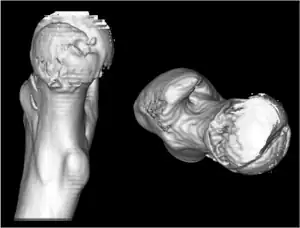

| Computed tomography reconstruction of isolated right femoral head showed three-dimensional morhpology of fracture. | |